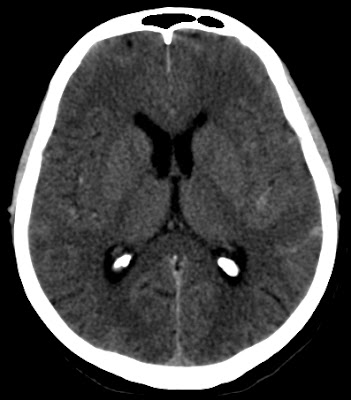

hyperdense perimesencephalic or prepontin CSFno evidence of aneurysmal bleeding000008199842013.04.06.